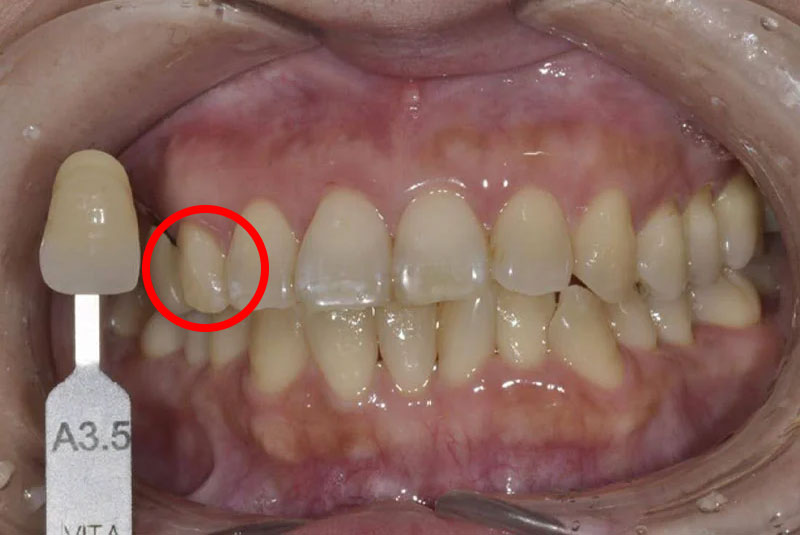

ウォーキングブリーチ直前

Shade guideとの比較写真